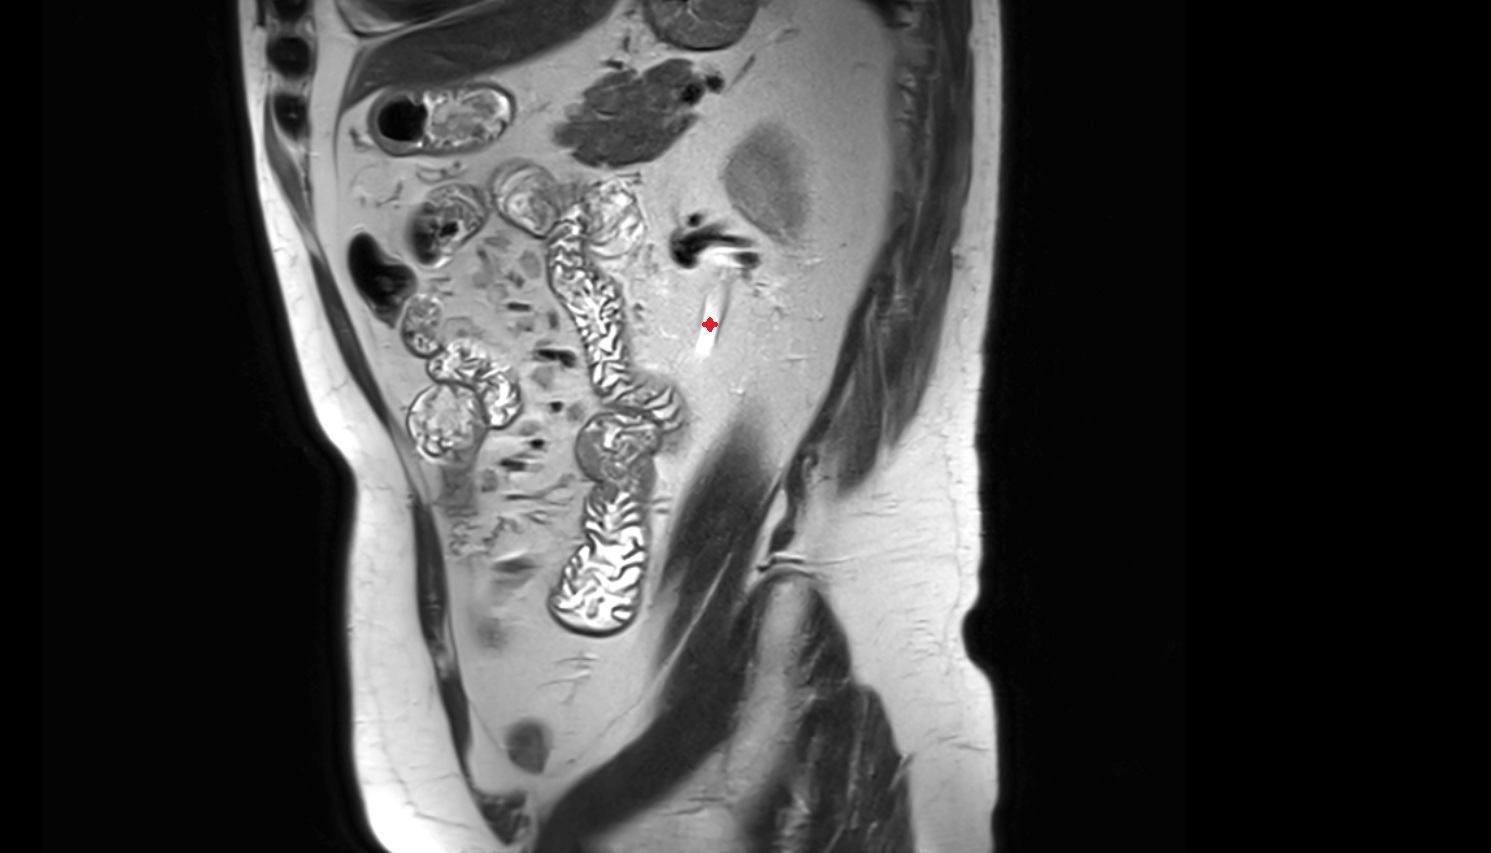

- Placenta

- Uterus (pregnancy)

- Amniotic fluid

- Umbilical cord

- Urinary Bladder in Pregnancy

- Cervix in Pregnancy

- Vagina in Pregnancy

- Fundus of uterus in pregnancy

- Fetal kidneys

- Fetal urinary bladder

- Fetal Liver

- Fetal small bowel